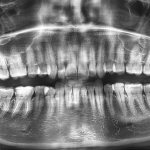

1. Диагностический осмотр. Пациент направляется на рентгенографию, при необходимости ему назначают лечение зубов или удаление подвижных единиц.